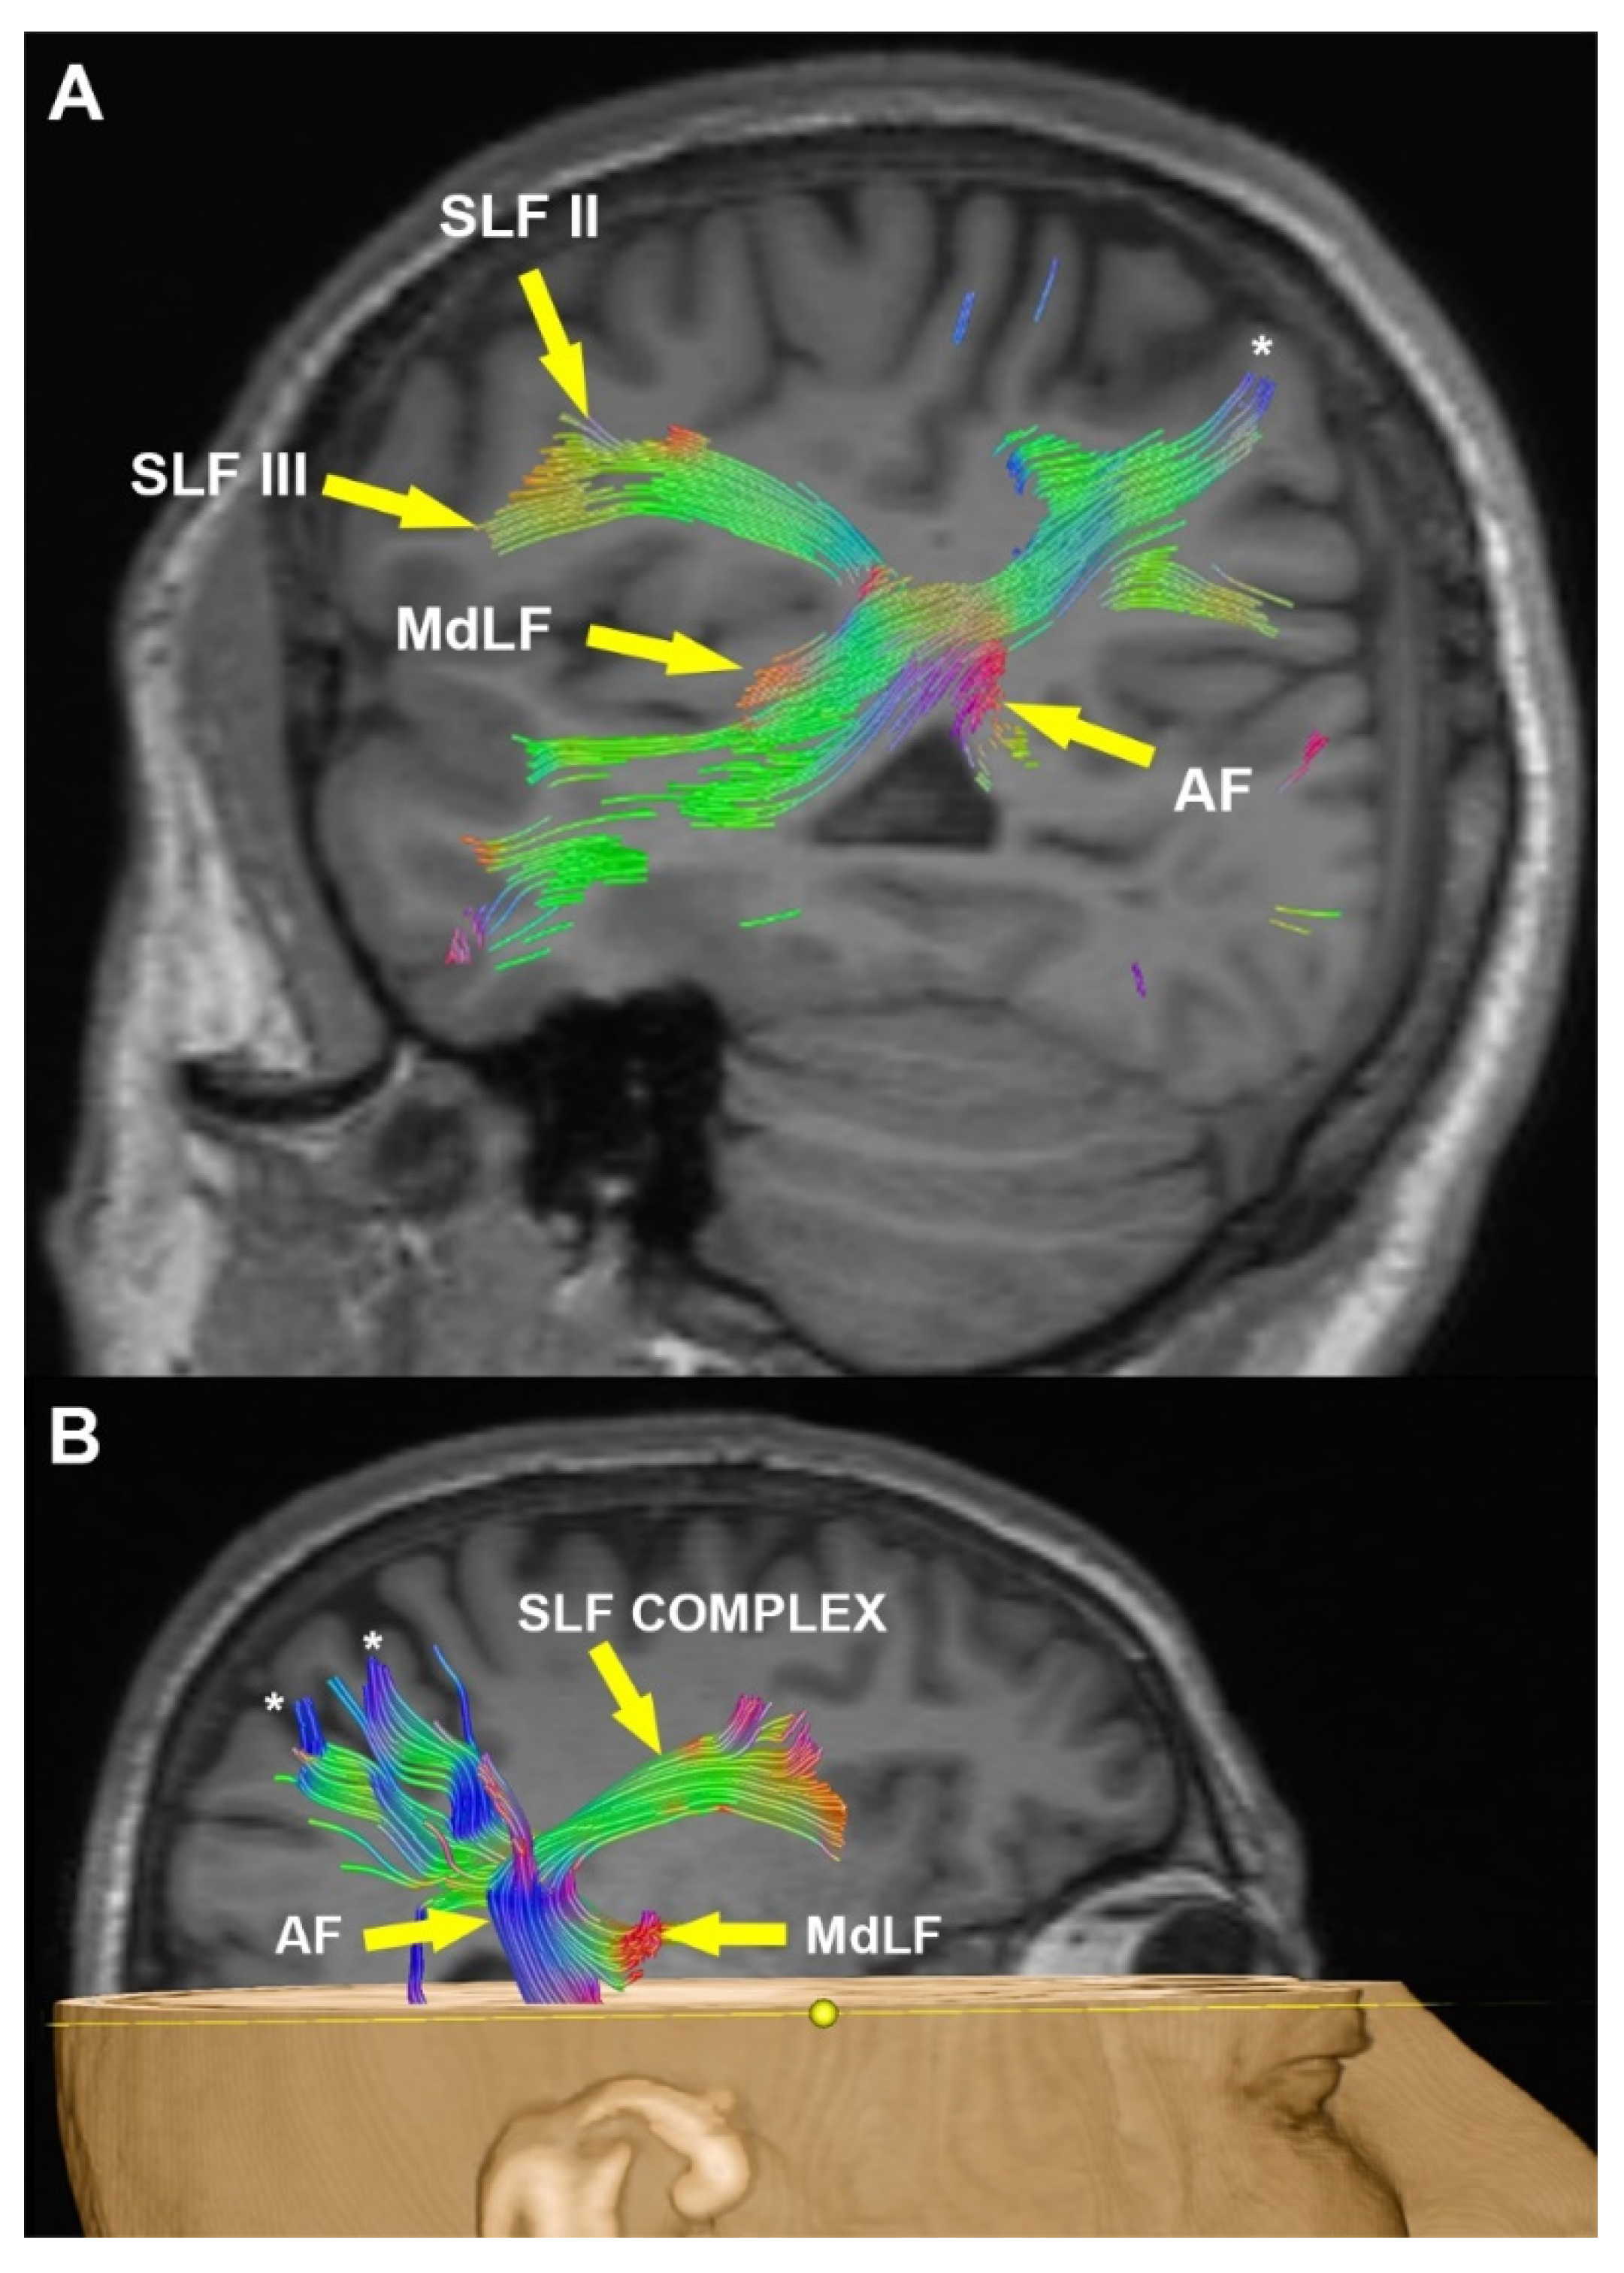

Supramarginal Gyrus and Angular Gyrus Subcortical Connections: A Microanatomical and Tractographic Study for Neurosurgeons

3.2. Radiological Examination